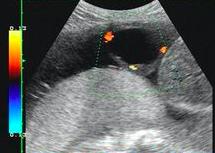

可是,最近的一次产检却让小黄皱起了眉头。原来,在做超声检查时候,医生发现胎儿的脐带有囊肿。

姜医生说:“孕妈还要定期到医院做超声检查,观察囊肿大小变化包括监测囊肿对脐血流的变化。 如果发现囊肿在逐渐长大,就要小心了。长大的囊肿会压迫脐带,影响胎儿的氧气供应和营养供应,严重的可能导致胎儿死亡。”